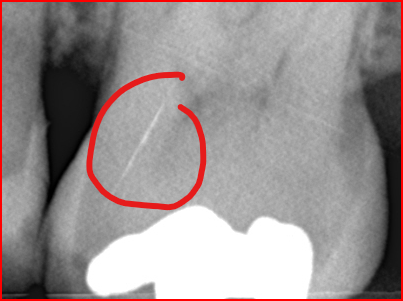

Sorry heb even gemarkeerd…

Oh wacht! Element 25! Dat is…

Mogelijk indicatie v necrose…

25, tweede kleine kies, verbreed parodontaal spleet. Mogelijk oorzaak v klachten. Soms straalt gevoeligheid door naar andere kiezen of zelfs naar de tegenovergestel kies in de onderkaak of visa versa.